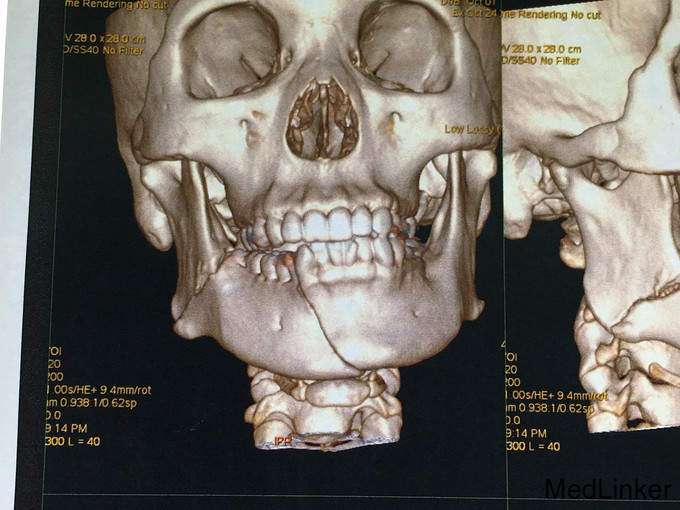

查体:神志清楚,右下颌体部见长约2.0cm开放创口,张口度1.5cm,咬合关系紊乱,右下唇麻木感,43,44间见明显骨折线,异常动度,48松动II,牙龈撕裂,右下颌肿胀,右侧髁状突冲击试验减弱,上颌骨无异常动度,于无异常。 辅查:CT,右下颌骨颏部及下颌角不骨折。

诊断:右下颌骨颏部及下颌角不骨折 治疗:右下颌骨颏部及下颌角部骨折经口内切开复位内固定。